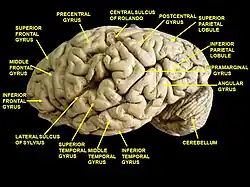

.png.webp) Superficial anatomy of the inferior parietal lobule.

LS: Lateral sulcus (Sylvian fissure), CS: Central sulcus, IPS: Intraparietal sulcus, STS:Superior temporal sulcus, PN: Preoccipital notch. | |

It is divided from rostral to caudal into two gyri:

- One, the supramarginal gyrus (BA 40), arches over the upturned end of the lateral fissure; it is continuous in front with the postcentral gyrus, and behind with the superior temporal gyrus.

- The second, the angular gyrus (BA 39), arches over the posterior end of the superior temporal sulcus, behind which it is continuous with the middle temporal gyrus.